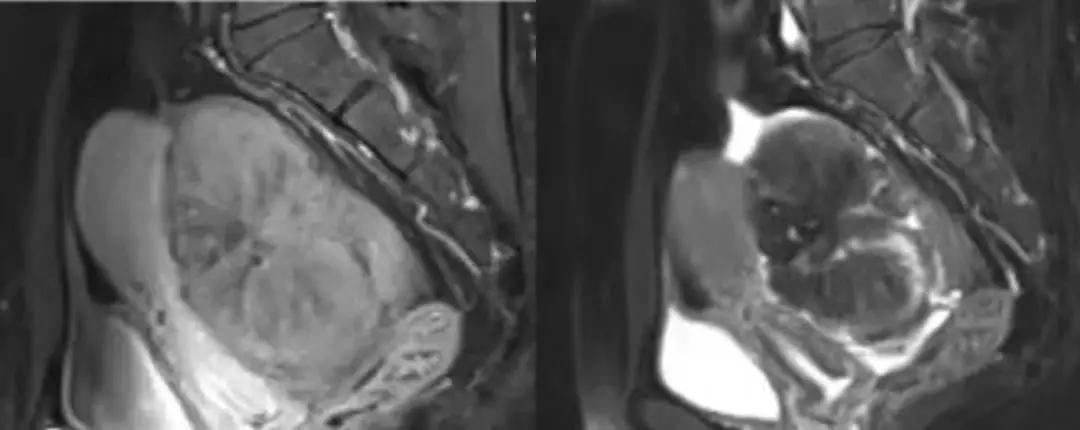

病例10

女,39 岁,体检发现盆腔肿块1月余

CA125:51U/ml

病理:左侧卵巢卵泡膜-纤维瘤